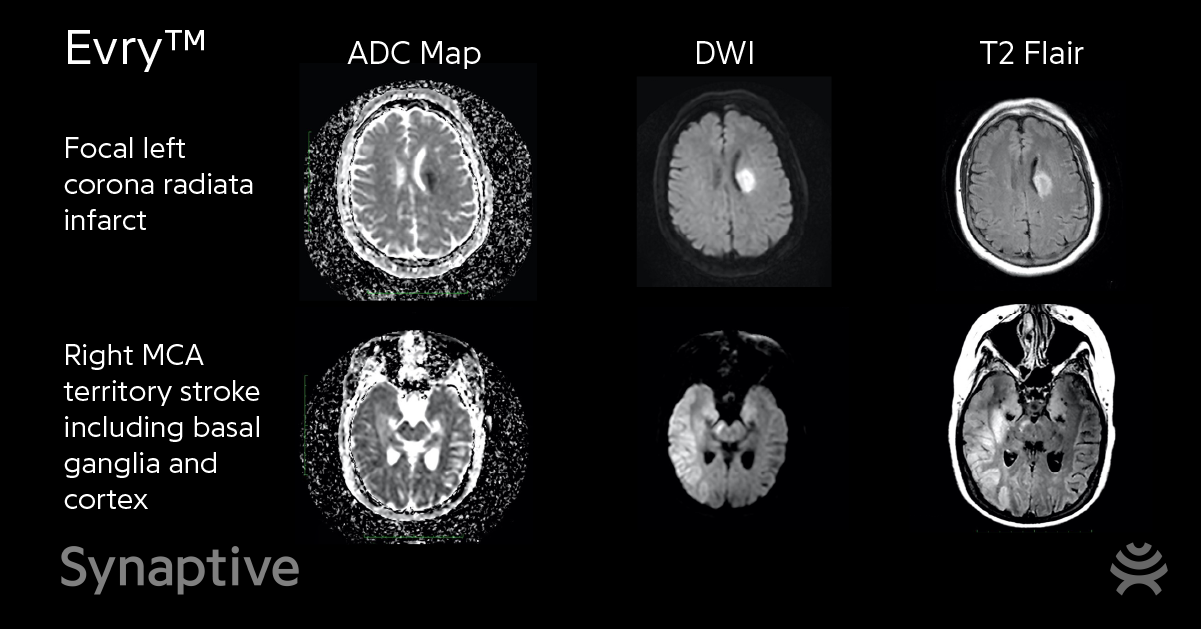

Our hospital partner, Nova Scotia Health’s Queen Elizabeth II Health Sciences Centre, has completed their first inpatient scans for stroke detection research with our 0.5 T MRI, Evry™.

We are pleased to be able to share two of the scans which include a focal left corona radiata infarct and a right MCA territory stroke including basal ganglia and cortex.